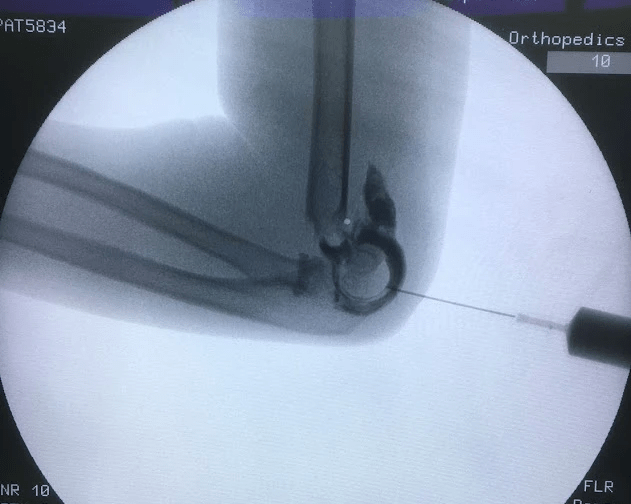

- 如果有位移則要進行復位及鋼針固定

- 如果合併有血管及神經問題,須儘快進行復位